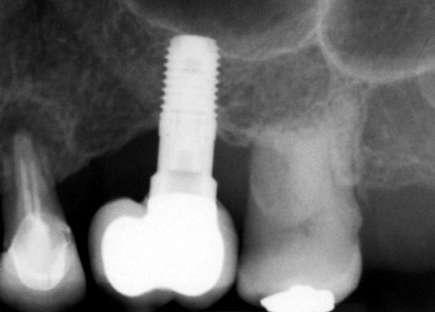

Figuras 3-6. Imágenes de un caso de prótesis atornillada en molar unitario inferior. Vemos el estado de los tejidos blandos gingivales tras la segunda fase y colocación del transepitelial unitario y la radiografía. En las imágenes inferiores (5 y 6) observamos el caso a los 4 años y 10 años de seguimiento, con estabilidad completa de los tejidos óseos peri-implantarios.

Figuras 7-10. En las dos imágenes superiores (7 y 8) observamos la realización de la prótesis cementada mediante un bioplilar fresado a la altura gingival con la radiografía antes del cementado de la corona. En las imágenes inferiores (9 y 10) vemos la prótesis a los 7 años de seguimiento y a los 9 años transformada en una prótesis atornillada al perderse la pieza anterior al implante y realizarse un puente con el nuevo implante. En este caso, el nivel óseo permanece estable con el paso del tiempo.